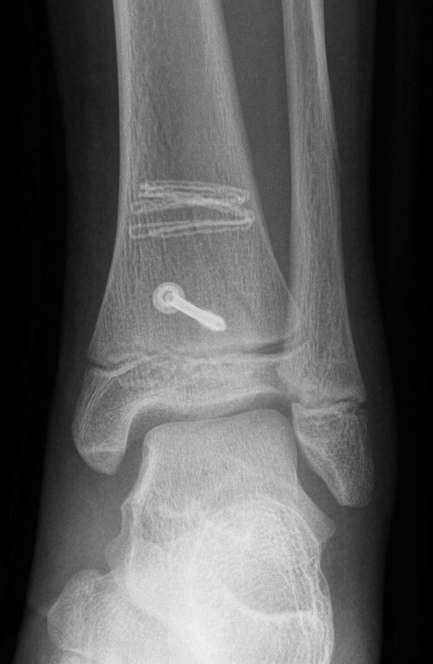

Ist die korrekte Stellung nur gegen einen federnden Widerstand zu erreichen, kann die Fraktur durch perkutane K-Drähte stabilisiert werden. Bei einer Fugenschaftfraktur mit großem Keil ist auch eine Schraubenosteosynthese möglich (Abbildungen 13 bis 14).

Behandlungsziel ist die exakte Rekonstruktion der Gelenkfläche sowie die Minimierung des Risikos einer späteren Wachstumsstörung. Dislozierte Frakturen werden offen reponiert, die Osteosynthese erfolgt mit einer Kleinfragmentschraube. Finden sich viele kleine Fragmente kann eine K-Draht Osteosynthese durchgeführt werden. Wird der Innenknöchel operiert, kann bei gleichzeitiger hochgradiger lateraler Instabilität eine Rekonstruktion des lateralen Bandapparats durchgeführt werden. Fibula Frakturen stellen sich meist spontan ein, sodass hier keine zusätzliche Osteosynthese notwendig ist.

Die häufig nicht dislozierten knöchernen Ausrisse können konservativ behandelt werden. Dislozierte Fragmente sollten operativ mit Kirschner-Drähten oder Schrauben fixiert werden (Abb. 32). Die Nachbehandlung umfasst eine 4-wöchige Entlastung im US-Gips. Eine Röntgenkontrolle erfolgt nach Gipsabnahme. Freies Gehen sollte nach 6 Wochen möglich sein. Danach ist auch eine sportliche Belastung des Sprunggelenks möglich (v. Laer 2013).

Eingebrachtes Osteosynthesematerial sollte vor der Vollbelastung entfernt werden.